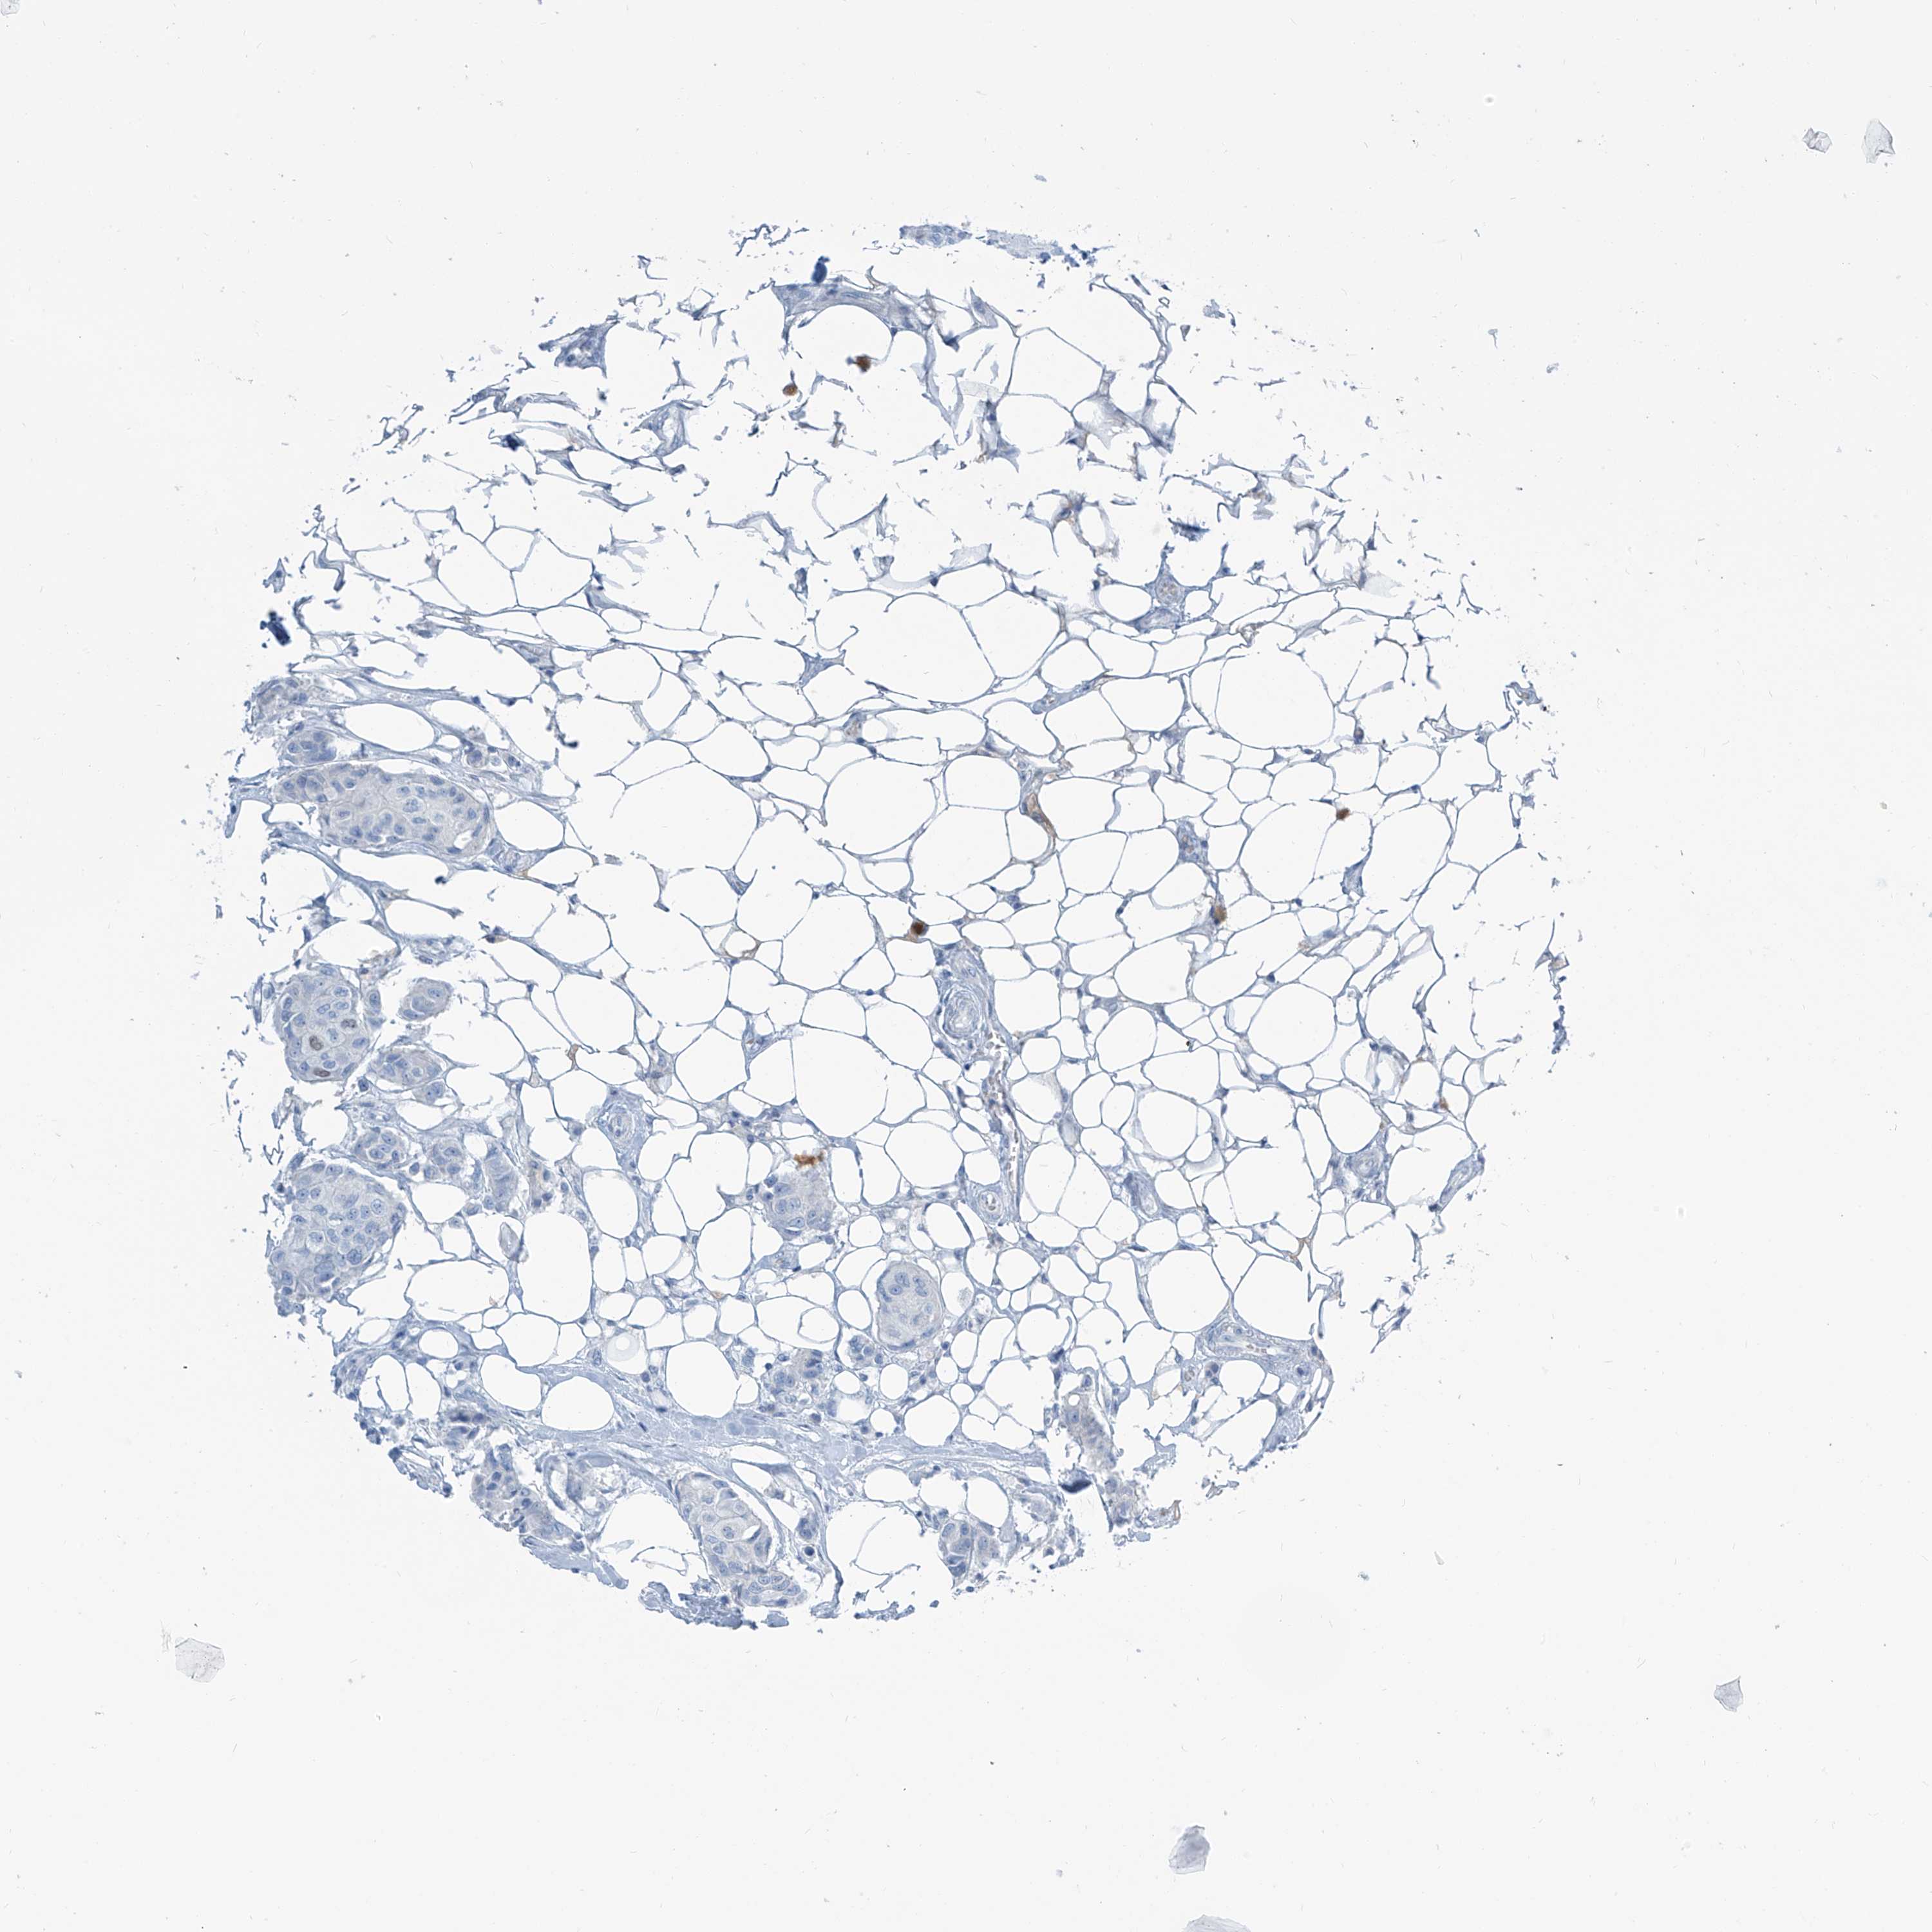

BRCA TCGA BRCA VALIDATION PROTEIN EXPRESSION

ANTIBODIES

AND

VALIDATION